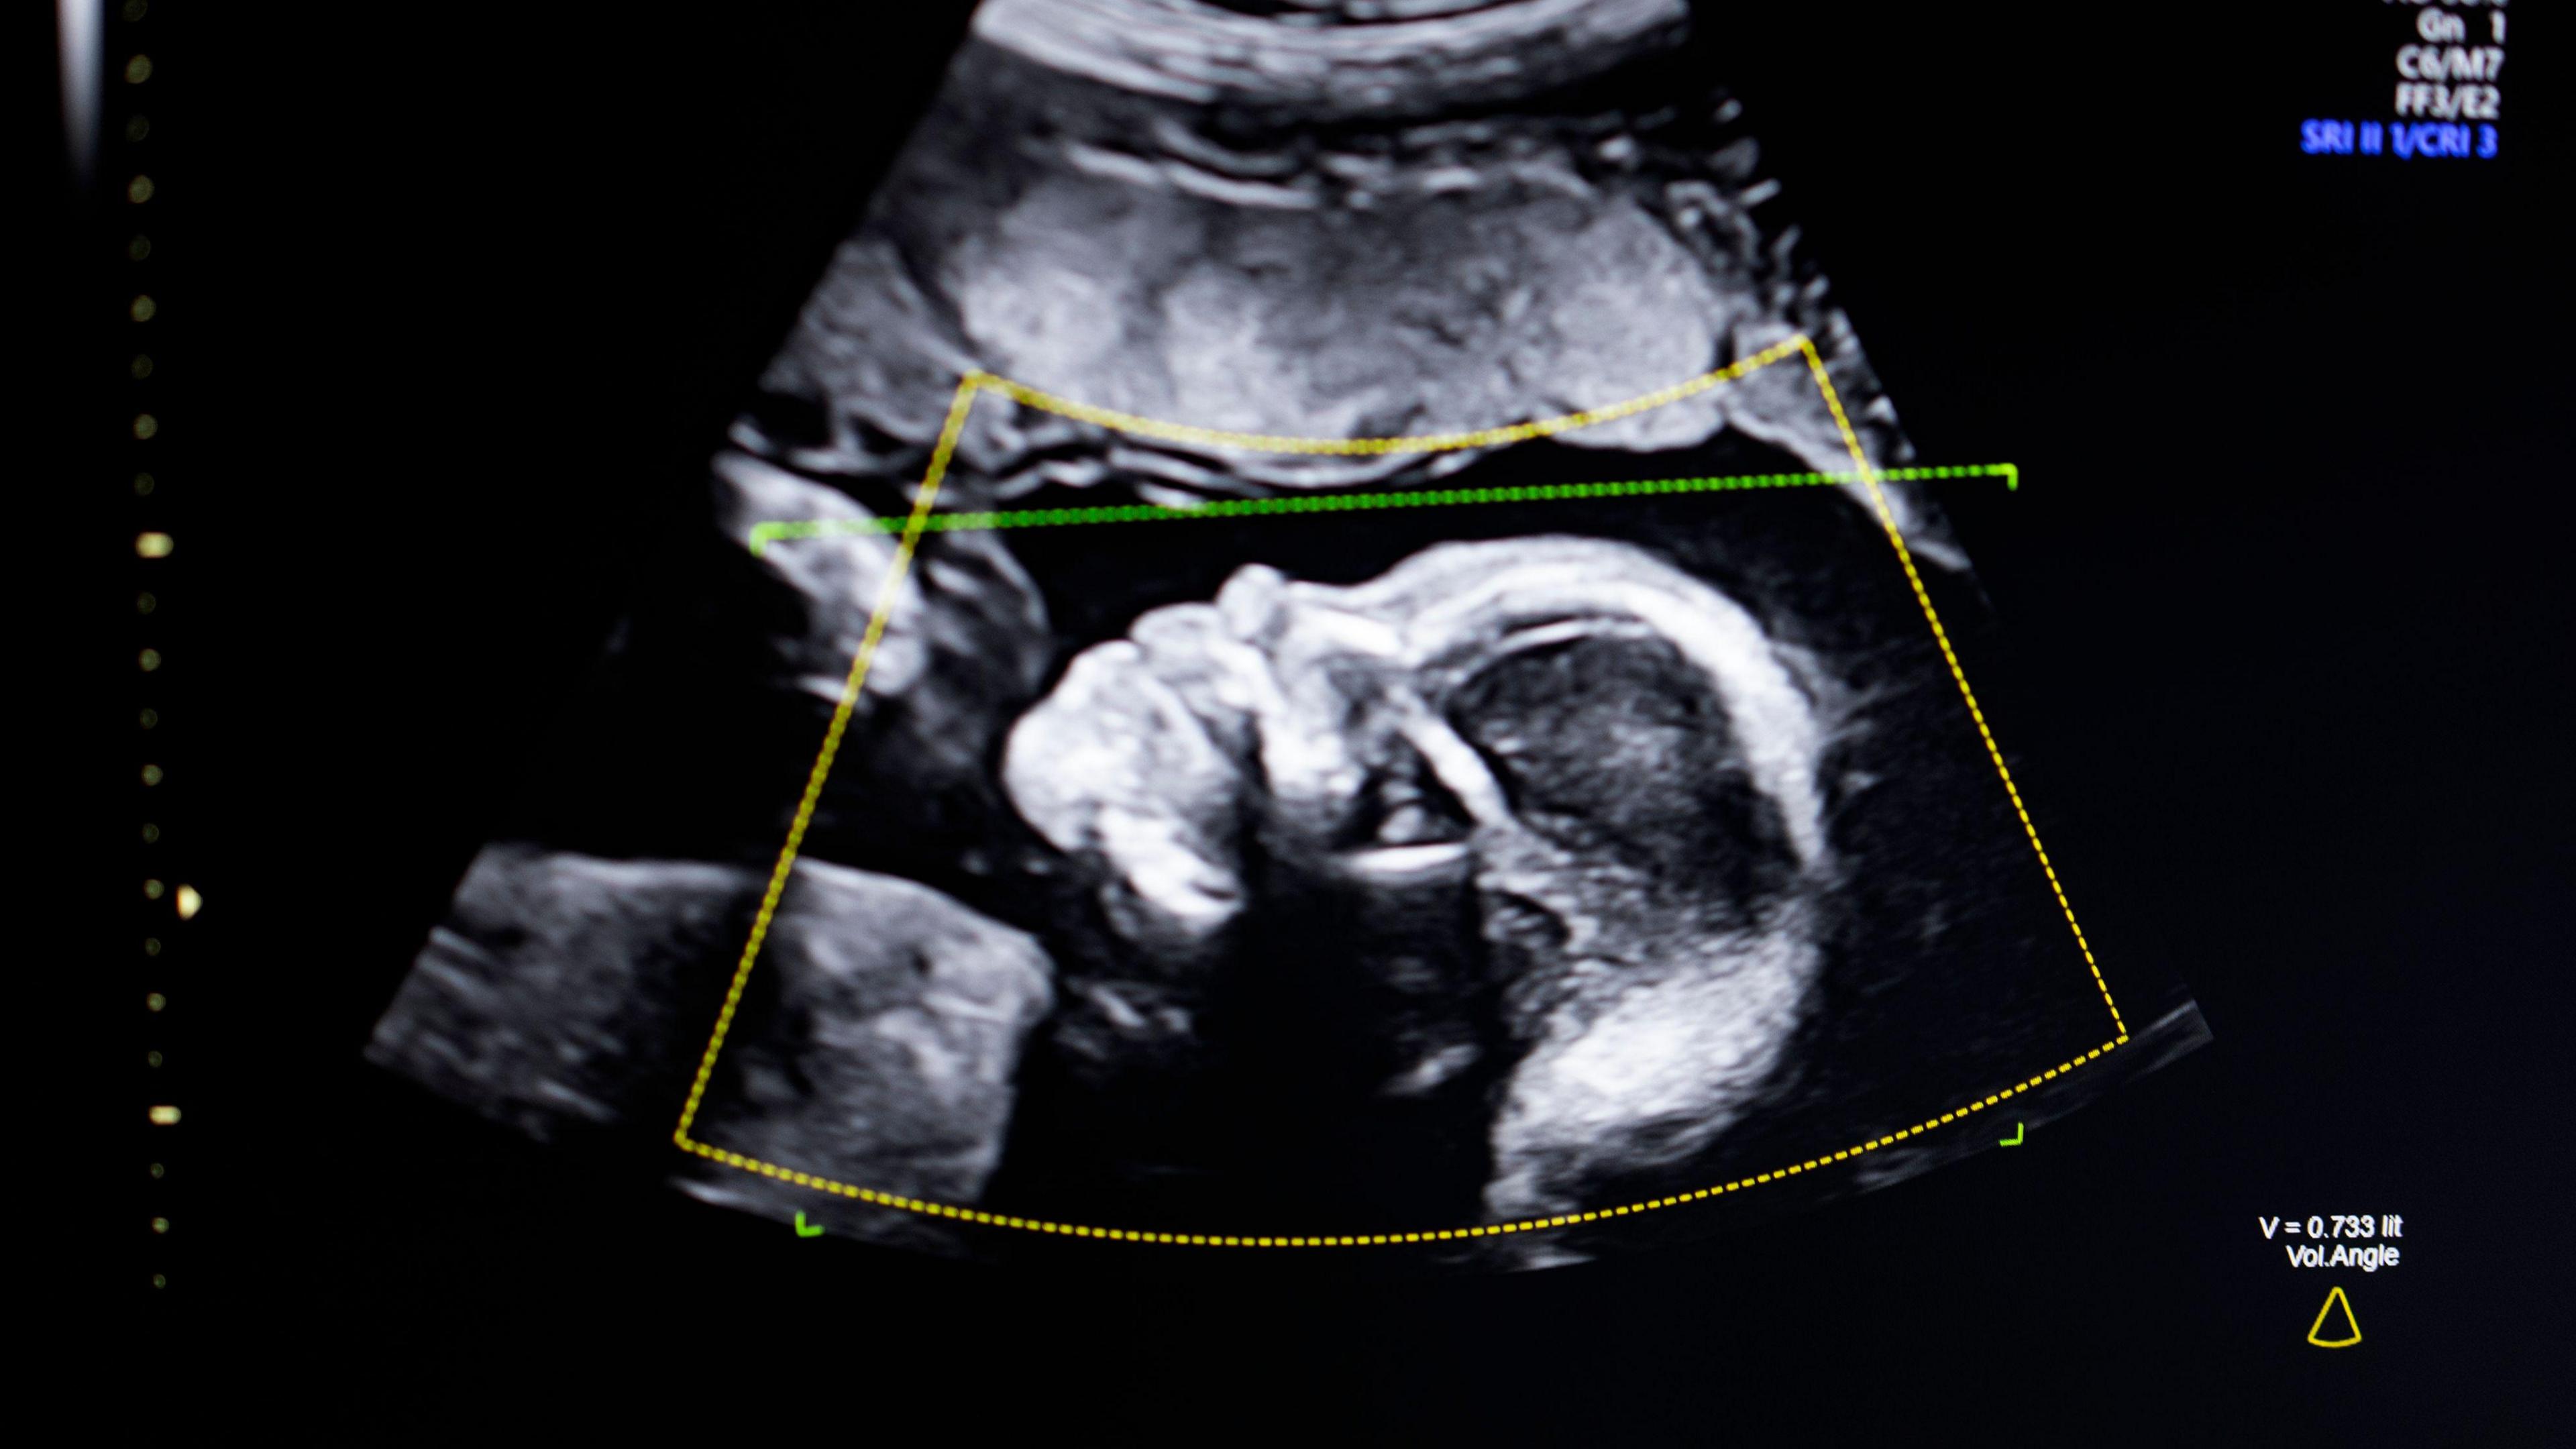

It is concerned that anyone using an ultrasound machine can call themselves a sonographer and offer the service - often sold as a reassurance, souvenir or sexing scan - ahead of the routine 20-week NHS check.

Private clinics often offer reassurance or sexing scans before the standard NHS anomaly scan which is normally offered between 18 and 21 weeks into the pregnancy